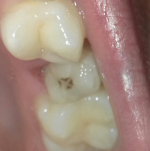

Осталась одна стенка зуба

После повреждения осталась лишь одна стенка? Такая ситуация не особо критична, ровно как и если у вас откололась небольшая часть зуба (рекомендуем прочитать: что делать, если кусочек зуба откололся?). В таких случаях восстановить здоровье десны и зубов можно с помощью:

- использования коронки,

- полного наращивания с использованием штифтов.

В варианте с наращиванием вам придется платить за штифты и материал, соответственно цена будет зависеть от материала. Чем хорош такой способ? После наращивания зуб будет выглядеть как родной и иметь идеальную форму, нервные каналы и корень зуба будут защищены от воздействия внешних факторов. При использовании высококачественных материалов данная конструкция никогда не отломится.

Запломбировали каналы. Можно ли поставить штифт, а не коронку, если осталась одна стенка жевательного зуба?

Ответить

Если большая часть коронковой части зуба разрушена, в данном случае осталась только одна стенка, то устанавливается штифт, а далее подбирается план лечения. Либо коронковая часть восстанавливается композиционным материалом, либо ортопедической конструкцией (коронкой, вкладкой). Но штифт в любом случае необходим, для придания прочности конструкции.